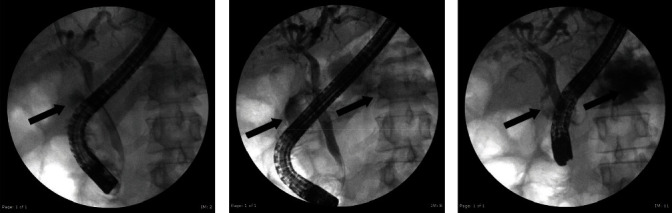

Background: Cholecystoenteric fistulae are rare complications of gallstone disease, with a reported incidence of 0.5% to 0.9% of cholecystectomies. Cholecystoduodenal is the most common fistula followed by cholecystocolonic fistulae. Summary: We report a case of pneumobilia resulting from a combined cholecystoduodenal and cholecystocolonic fistulae treated with a laparoscopic subtotal cholecystectomy and open repair of the enteric fistulae. Conclusion: Combined cholecystoduodenal and cholecystocolonic fistulae are an extremely rare complication of gallstone disease, and meticulous preoperative planning and operative dexterity are needed to safely manage these unusual fistulae.